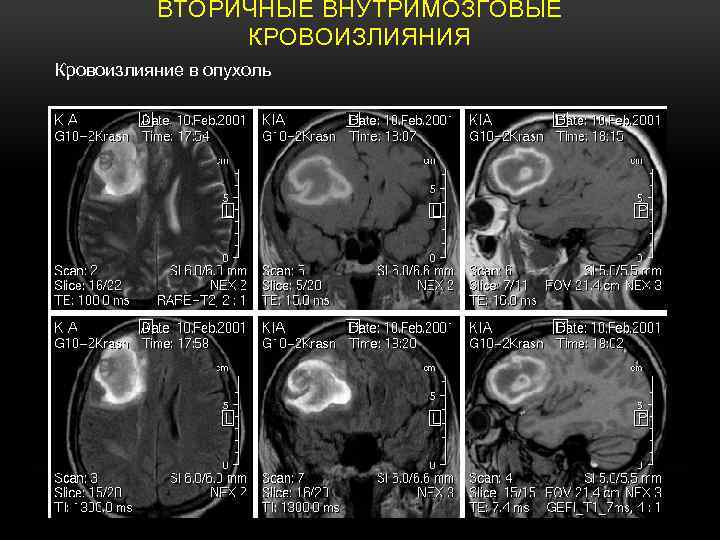

ВТОРИЧНЫЕ ВНУТРИМОЗГОВЫЕ КРОВОИЗЛИЯНИЯ Кровоизлияние в опухоль

КРОВОИЗЛИЯНИЯ В МЕТАСТАЗЫ АДЕНОКАРЦИНОМЫ T 1 - W ; SE PD - W; TSE T 2 -W; TSE